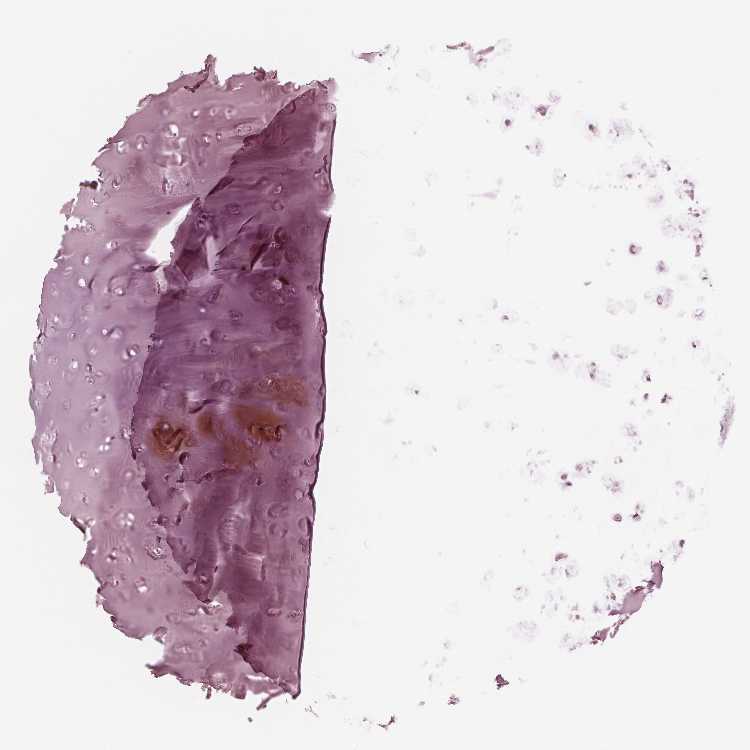

SOFT TISSUE 1 - Antibody stainingi

Antibody staining in the annotated cell types in the current human tissue is reported as not detected, low, medium, or high, based on conventional immunohistochemistry profiling in selected tissues. This score is based on the combination of the staining intensity and fraction of stained cells.

Each image is clickable and will lead to virtual microscopy that enables deeper exploration of all samples and also displays staining intensity scores, fraction scores and subcellular localization as well as patient and tissue information for each sample.

Antibody HPA020108Antibody HPA029473Antibody CAB016762

Chondrocytes Not detectedNot detectedNot detected

Fibroblasts Not detectedNot detectedNot detected

Peripheral nerve --Not detected